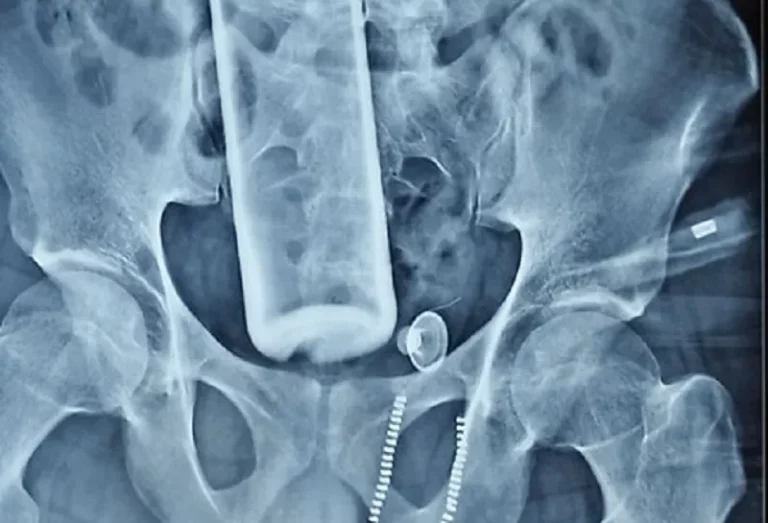

जनस्वास्थ्य सरोकार, काठमाडौँ । पेटभित्र रक्सीको बोतल पसेको बिरामीको सफल शल्यक्रिया भएको छ । पुरानो मेडिकल कलेज भरतपुरमा युवकको पेटभित्र पसेको रक्सीको बोतल बाहिर निकालिएको हो ।

रौतहटको गुजरा नगरपालिका–९ अमतबा टोलका २६ वर्षीय युवकको मलद्धारबाट रक्सीको बोतल पेटमा छिरेको थियो ।

अस्पतालको अनुसार युवकको पेट चिरेर हेर्दा ठुलो आन्द्रा फुटेर बोतल बाहिर निस्केको अवस्थामा भेटिएको हो । शल्यक्रियापछि युवकको अवस्था राम्रो भएको छ । उनको होस आएको छ । युवकले जानीजानी बोतल भित्र पसाएको चिकित्सकहरुको अनुमान छ ।

डा. बेल्बासे नेतृत्वको डा.सागर खतिवडा, डा. विनय तिमल्सिना, सुशील भुजेल, राजेश यादव, असिम, मोनालिसाको टिमले साढे दुई घन्टा लगाएर शल्यक्रिया गरी बोतल निकालेको थियो। बिरामीको अवस्था जटिल भए पनि मलद्वारको मुख्य भाग ८० प्रतिशत सुरक्षित भएकाले अवस्था सामान्य हुने चिकित्सकको भनाइ छ ।